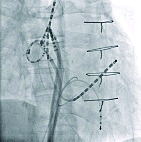

肺静脈隔離治療・透視画像

右前斜位

X線透視画像を確認しながら、医師はカテーテル治療を行う

足の付け根の静脈や首の静脈からX線透視画像を確認しながらカテーテルを心臓まで挿入し、心臓内に数本の電極カテーテルを留置します。この電極カテーテルから得られる電気の流れなどを確認しながら、アブレーションを行っていきます。実際に記録される電位に加えて、胸部に貼ったパッチと心房内のリングカテーテルから位置情報をとり、モニターに心房を中心とした三次元のカラーマッピング画像を描出します。図は肺静脈隔離術後の左心房の三次元マッピングですが、焼灼を終えた低電位領域は赤、高電位領域は紫で表示され、肺静脈の隔離が改めて確認できるのです。